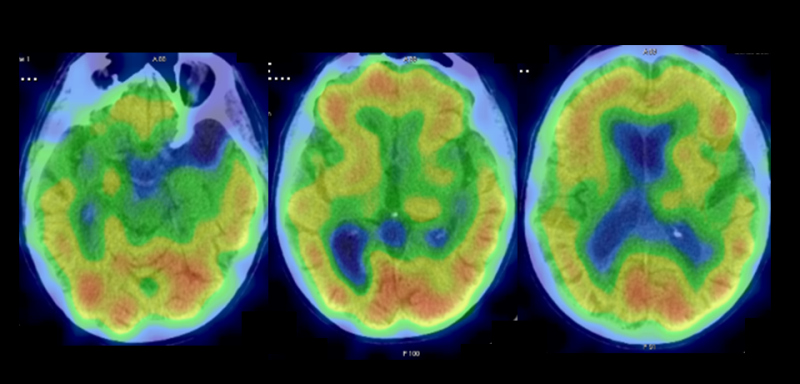

Se complementó con estudio PET Beta- amiloide (18F-Florbetaben). En las imágenes precoces post-inyección que aportan información de la perfusión cerebral, no se apreciaron alteraciones significativas en las diferentes estructuras corticales que conforman ambos hemisferios cerebrales, así como tampoco a nivel subcortical ni en fosa posterior (fig 3). En las imágenes tardías post-inyección que informan sobre la densidad de placa neurítica de beta-amiloide (fig. 4) se observó pérdida de la diferenciación entre sustancia gris y sustancia blanca en todas las regiones claves. La sustancia gris de dichas regiones muestra una importante captación del trazador, superior a la de la sustancia blanca, abarcando la mayoría de los cortes y en algunas zonas llegando incluso al margen cortical exterior. Presenta una puntuación CCRT (captación cortical regional de trazador) de 3. El estudio se considera globalmente como positivo con un CPAE grado 3 (exploración con depósitos importantes de beta-amiloide).

La orientación diagnóstica fue demencia tipo Alzheimer (DTA) típica según criterios IWG-2, dado que presenta: a) fenotipo clínico específico con afectación precoz de memoria episódica asociada a cambios conductuales, que sugieren el diagnóstico de Deterioro Cognitivo Leve Amnésico, y b) evidencia "in vivo" de patología tipo Alzheimer mediante estudio PET amiloide.